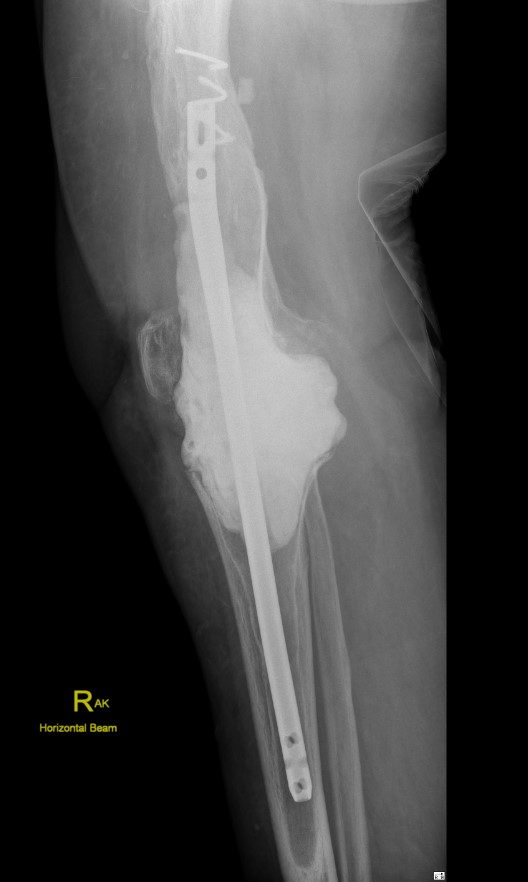

A. Bridging nail

Bridging nail

Modular nail

Long fusion nail

Design

Insert through proximal femur

Incorporates

- femoral curvature

- knee valgus

- different intramedullary diameter between femur and tibia